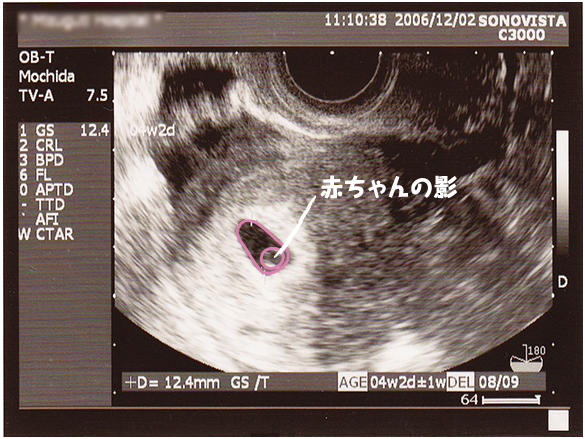

チャーミー小結さんの妊娠5週目のエコー写真 2D・3Dのエコー写真で見る「私と赤ちゃんの実録260日」 妊娠検査薬で陽性反応が出た翌日、病院を受診して最初に撮ったエコー写真です。 この時点で妊娠5週目。 初めて見る画像でしたが、モニターに映った・妊娠初期症状 ・妊娠した時の基礎体温 ・つわり(妊娠悪阻)を乗り切る ・妊娠後の栄養とサプリメント ・葉酸について ・二分脊椎症 ・産院選びのポイント ・双子って? 胎児の成長(エコー写真あり) ・妊娠 1ヶ月(妊娠超初期) ・妊娠 2ヶ月(4~7週 心拍確認はいつ?妊娠初期の赤ちゃんエコー写真と経過体験談 妊娠後期の赤ちゃんエコー写真と経過体験談 スポンサーリンク 今週の人気記事 年最新妊婦さんが無料でもらえる応募者全員プレゼントまとめ こどもちゃれんじの無料請求方法まとめ期間限定ファミリア

妊娠5週目 胎嚢の大きさ エコー写真 つわり症状や流産のこと 妊娠初期 All About